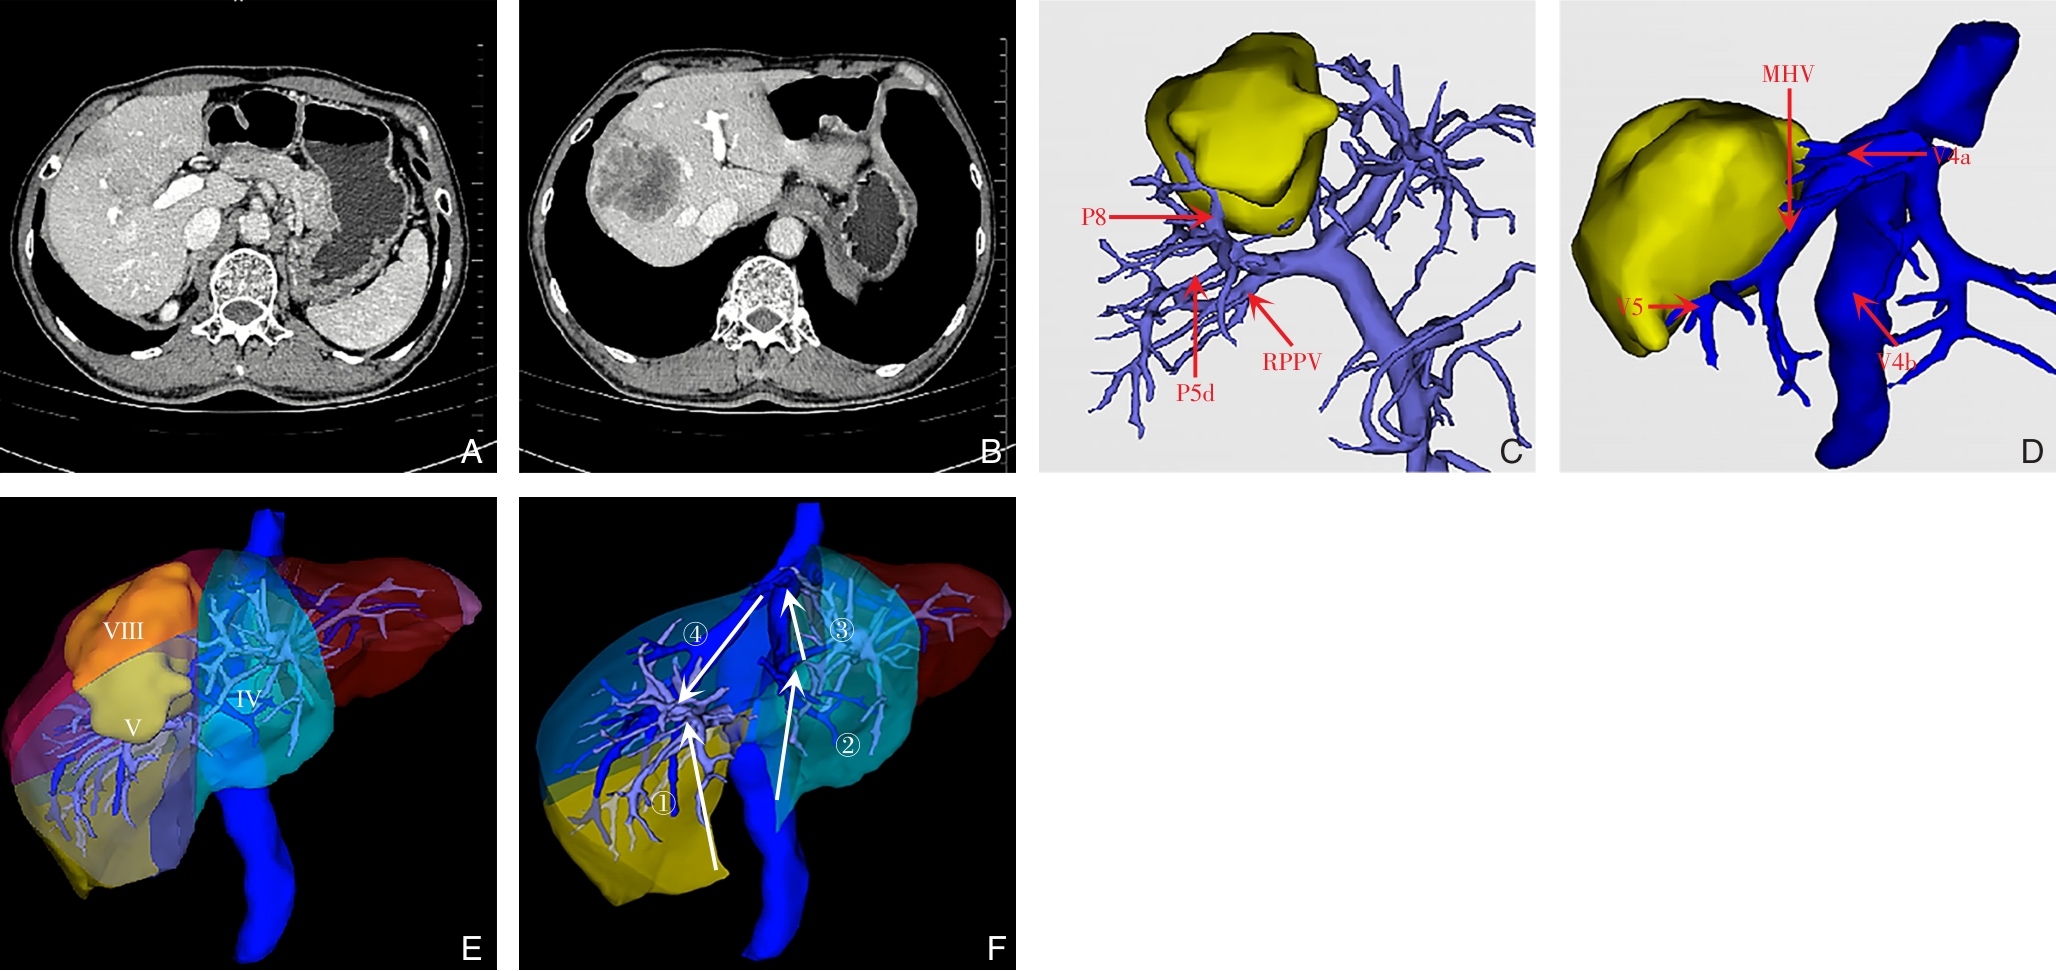

Background and Aims Precise identification and control of segmental Glissonian pedicles are fundamental to laparoscopic anatomical liver segmentectomy. However, marked anatomical variations, particularly in the right hemiliver, pose significant technical challenges. Based on the anatomical concept of the hepatic Laennec's membrane, this study aimed to systematically investigate the applied anatomy of Glissonian pedicles at the hepatic hilum and to establish practical anatomical landmarks for laparoscopic anatomical liver resection.Methods Six intact adult human liver specimens without macroscopic lesions were dissected under the guidance of the Laennec's membrane concept. The segmental Glissonian pedicles at the first porta hepatis were meticulously isolated, and the intervening liver parenchyma was removed. The origin, branching patterns, and spatial courses of Glissonian pedicles in each hepatic segment were analyzed. For the right hemiliver, a localization system consisting of four anatomical landmarks, two reference lines, and four characteristic angles was proposed and quantitatively evaluated using specimen measurements combined with CT imaging and three-dimensional liver reconstruction.Results The intrahepatic Glissonian system demonstrated both consistent patterns and pronounced individual variations. In the left hemiliver, the Glissonian pedicles of segments Ⅱ and Ⅲ usually arose independently, while segment Ⅳ commonly presented a bifurcated pattern with occasional multiple branches. In contrast, the right hemiliver showed substantial variability: segment V pedicles were frequently multibranched and often received contributions from segment Ⅵ; segment Ⅵ served as a pivotal pedicle with multiple branches contributing to segments V and Ⅶ; segment Ⅶ most commonly originated from the root of the right posterior pedicle, although in some cases it was formed by distal extensions of segment Ⅵ; segment Ⅷ pedicles were relatively constant in morphology, typically consisting of one or two branches. The proposed anatomical landmarks and quantitative parameters enabled clearer spatial localization of segmental Glissonian pedicles in the right liver.Conclusion Systematic dissection of segmental Glissonian pedicles guided by the Laennec's membrane concept, together with a quantitative anatomical landmark system, enhances the understanding of their spatial anatomy and variations. This approach provides practical and reliable anatomical guidance for precise and safe laparoscopic anatomical liver segmentectomy.